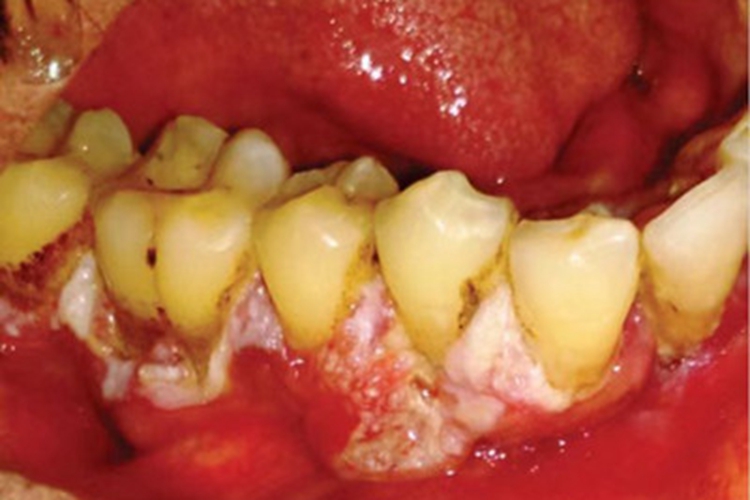

牙龈癌可导致牙龈局部出现异常凸起的肿块,表面可破溃、糜烂形成大小不一的溃疡,形状不规则,表面发白,并覆有一层假膜,可呈粉白色、黄白色,颜色分布不均。溃疡的深浅不一,表面可出血,也可覆有食物残渣,而呈污浊样,自觉有口腔异物感等不适。

牙龈癌的发生可能与口腔卫生不良、不良修复体或义齿修复,以及饮食习惯等因素有关,这些致病因素可导致牙龈局部的上皮细胞发生基因突变,引起上皮增生,使局部出现异常凸起的肿块,进食质地较硬的食物或是牙齿咬伤等均可导致表面破溃、糜烂形成溃疡。